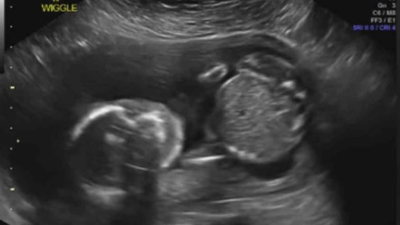

Mira: Ultrasonido muestra a un bebé dándose un puño en la cara